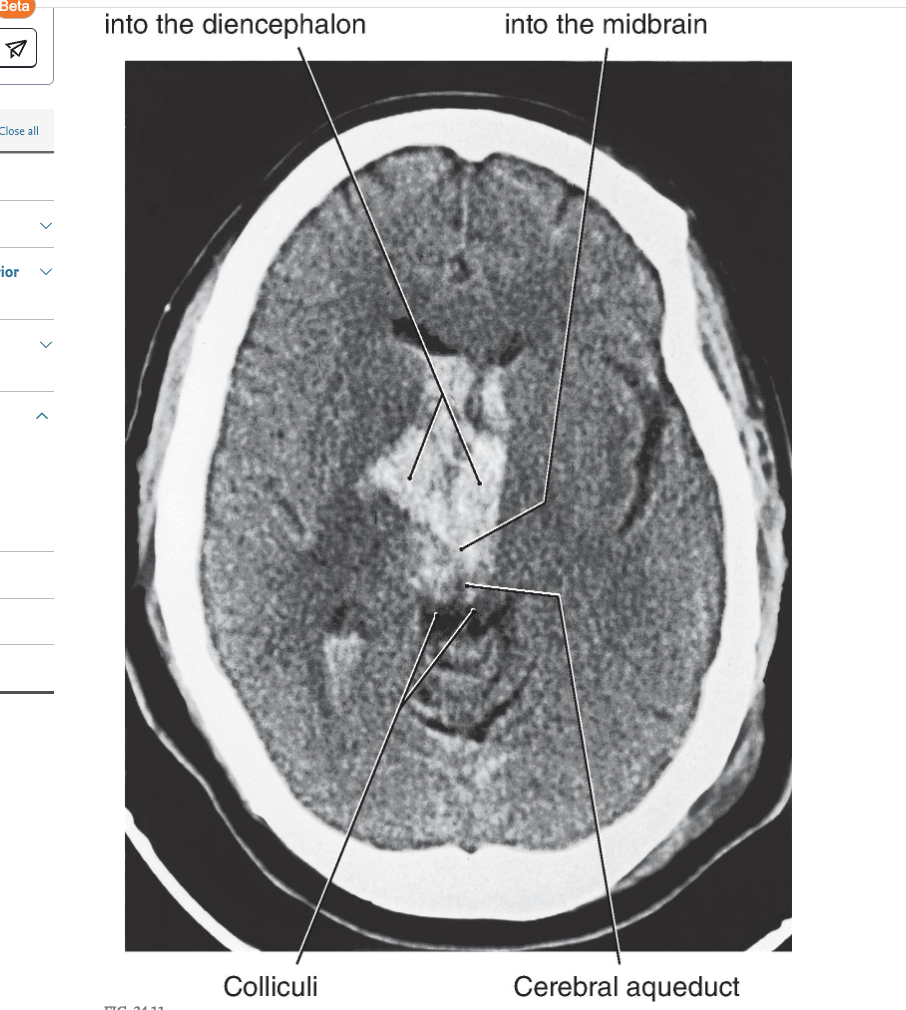

Decerebration

Central (or transtentorial ) herniation may be seen in patients with large tumors in the hemisphere or after a large hemorrhage in the hemisphere ( Figs. 24.11 and 24.12 ). In the diencephalic stage (before herniation through the tentorial notch), the patient may have a decreased level of consciousness, lethargy, small but poorly reactive pupils, and eye movement disorders. In addition, the withdrawal reflex to noxious stimuli is intact, reflexes are hyperactive, and there is a bilateral Babinski response. Once the herniation occurs, there is a rapid decline. The patient exhibits decerebrate posture, ( Fig. 24.12 ) is comatose, has dilated and fixed (do not react to light) pupils, and eye movement is absent. As the damage extends downward through the midbrain, respiration is compromised ( Cheyne-Stokes, tachypnea, followed by shallow rapid rates), and survival is highly unlikely.